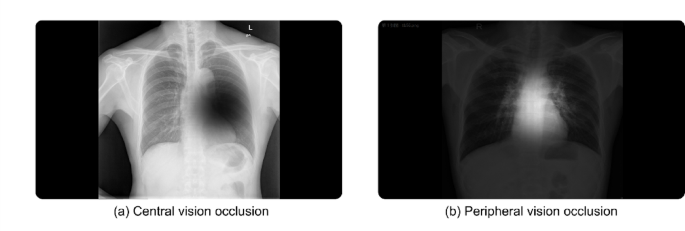

To achieve real-time occlusion of peripheral or central vision, this study designed two types of masks: one for occluding central vision and one for occluding peripheral vision. The central vision occlusion mask consisted of a black circular patch positioned at the center, the circular occlusion area with a radius of 400 pixels. The feathering value was set to 100 pixels. Feathering was applied to prevent harsh edges that could create noticeable dividing lines in the visual field, thus minimizing unnecessary visual interference. In contrast, the peripheral vision occlusion mask consisted of a transparent circular hole at the center, with the same parameters as the central vision occlusion mask (Fig. 2). The center of the mask was linked to the coordinates of the mouse cursor through programming, with the cursor movement being controlled by GazePointer (Fig. 3). This design ensured that, regardless of the direction of eye movement, the system could occlude the specified visual area. In a pre-experiment, participants were exposed to six gradient versions of the mask, with opacities ranging from 50 to 100%. The results indicated that participants experienced significant discomfort when the opacity exceeded 80%. As a result, the mask opacity was set to 80% to balance optimal visual occlusion with minimal discomfort.